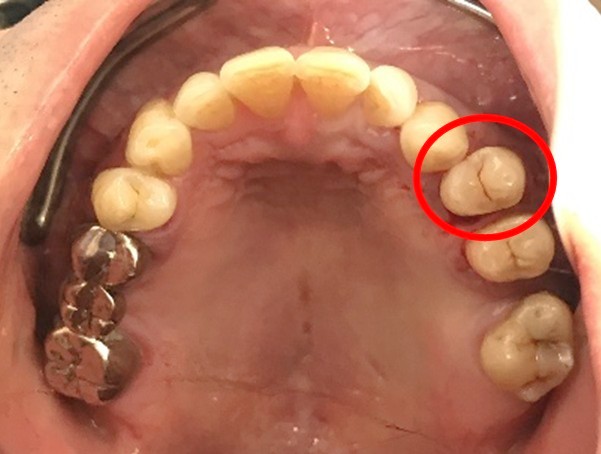

右上(第2小臼歯)の臭いが気になる。

治療内容

レントゲンで詳しく診てみると、歯根が真っ二つに割れていることがわかりました。臭いは、割れているために炎症を引き起こし、そこからの膿が原因でした。保存することができず抜歯しました。抜歯後、インプラントを埋入しました。

所感

抜歯後、ブリッジ、部分入れ歯の選択肢もありましたが、2013年に右下にインプラント治療をし、インプラントの良さを十分に理解しておられましたので、今回も1本歯を失ったところにインプラント治療を希望されました。歯根破折が原因で抜歯になった方ですので、もしブリッジにしていたら再度歯根の破折を引き起こし、さらに歯を失う可能性が、高い方でした。インプラントは、それ自身が単体で植立し、単独で咬合力を負担します。ブリッジや部分入れ歯のように他の歯に歯がない部分の負担を負わせることがないので、他の歯を守ります。インプラントにして正解だと考えます。今回もX-Guideを使った埋入で、安心安全に行うことができました。

インプラント1本:¥363,000(税込)

Before

歯根が真っ二つに割れていました

抜いた歯

【抜歯後】

After